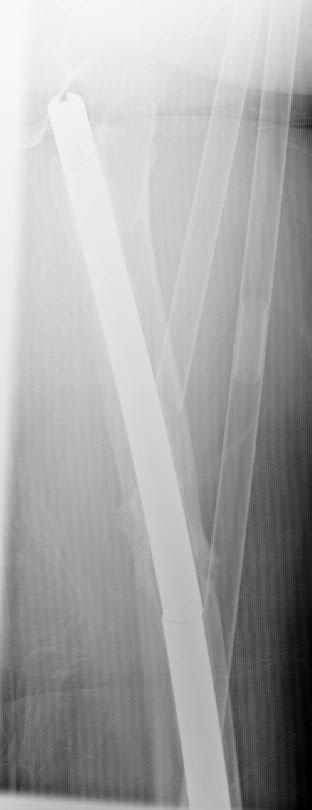

May I have some advice on the following case? Middle aged woman, No chronic medical problems, +tobacco use - but she promises she's going to quit! Original MVC in late 1990's, initial rod failed, and 2 subsequent exchanges failed (most recently shown in attached jpgs.)

Most recent one (6/2002) was apparently an open nailing to remove last broken nail, but no grafting was performed in conjunction. Now sent to me with broken 14mm R/T nail in place.WBC, Hgb, Chemistries normal.ESR 34CRP 4.2No other apparent locus of infection.I was considering a staged approach - removing nail and screws and obtaining cultures.If negative, proceed with exchange nailing with open grafting +/- BMP, But how best to deal with that pedestal distally and avoid anterior breech near patella? If positive cultures, what would be best option?Thanks. Tom Schaller Kalamazoo, MI.

In my opinion, there is no nail strong enough to tolerate a varus deformity of femur after nailing. The AP view of the distal femur shows that the femur has been repeatedly nailed in varus. The tip of the nail is short and lateral in distal lateral metaphysis. It should be central over the intercondylar notch and buried in the distal epiphyseal scar. This has resulted in constant bending forces on the nail (see the "windshield wiper" sign) and its eventual fatigue failure.